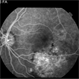

- macular choroidal osteoma

- Fundus camera

- Macular choroidal osteoma in a 29-year-old woman